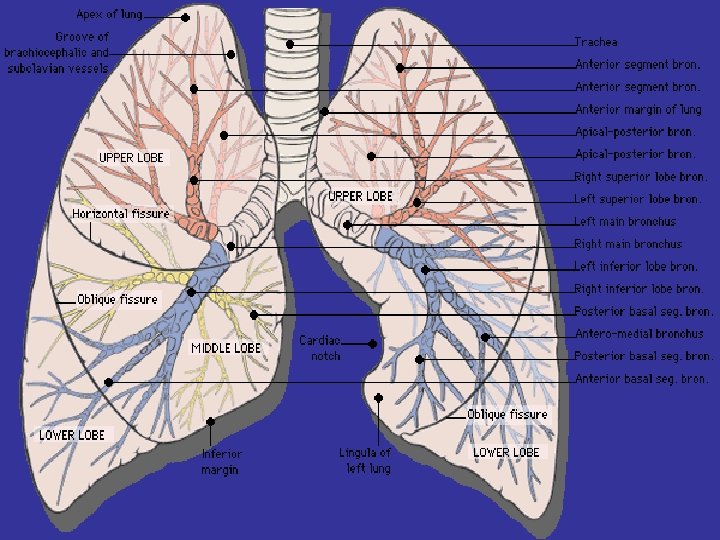

Lobes and Fissures

How to read a chest x ray ? • 1 - chest wall, bones

How to read a chest x ray ? • 1 - chest wall, bones and abdomen * bones; lesions or fractures * soft tissue ; mastectomy or soft tissue tumors • 2 - heart and mediastinum * trachea ; position & caliber * hila : lymphadenopathy * mediastinum contour : ? mass * heart : cardiac configuration • 3 - lungs opacity or lucency